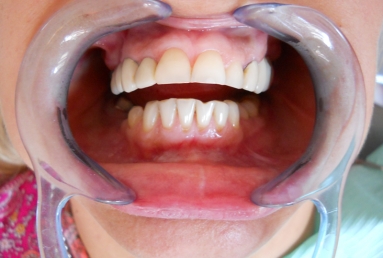

After treatment:

– zirconium/ceramic bridge in the lateral right maxillary area

– two implants and zirconium/ceramic bridge in the lateral left maxillary area

– full ceramic individual crowns in the frontal maxillary area, correcting at the same time the occlusion and the position of the frontal teeth.

– the lower arch was restored with a zirconium/ceramic bridge in the lateral right area and composite esthetic fillings + teeth whitening for the rest of the natural teeth.